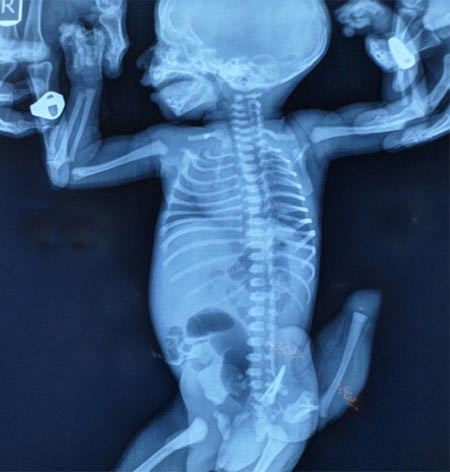

Khi mới chỉ 5 ngày tuổi, một trẻ sơ sinh ở Ấn Độ đã phải trải qua cuộc phẫu thuật cắt chiếc "đuôi" dài 12cm của em.

Các bác sĩ xác định, chiếc đuôi dị thường củacậu bé sơ sinh thực chất là người anh em song sinh dính liền, phát triển bất đốixứng và chưa hoàn thiện về mặt giải phẫu học.

Nếu không được chữa trị, chiếc đuôi có thể trở thành khối ung thư. Vì vậy,với sự đồng ý của gia đình, các bác sĩ tại bệnh viện Aarna ở Ahmedabad, tây bắcẤn Độ đã quyết định tiến hành phẫu thuật "cắt đuôi" cho cậu bé.

Bé sơ sinh 5 ngày tuổi rốt cuộc đã trải qua cuộc phẫu thuật kéo dài 4 tiếngđồng hồ để loại bỏ chiếc đuôi nặng 350g, mặc dù việc giữ lại nó có thể đem lạicho em một cuộc sống được tôn sùng ở Ấn Độ.

Tiến sĩ Rohit Joshi, giám đốc bệnh viện tiến hành phẫu thuật cho con côPatel, giải thích, trường hợp song sinh dính liền bất đối xứng như của cậu bénày rất khác với các ca song sinh dính liền đối xứng, vì chúng không có các kếtnối quan trọng ở hệ thống mạch dẫn truyền, ruột hay các xương. Y học ghi nhậnhiện tượng song sinh dính liền đối xứng phổ biến hơn ở Ấn Độ và châu Phi.